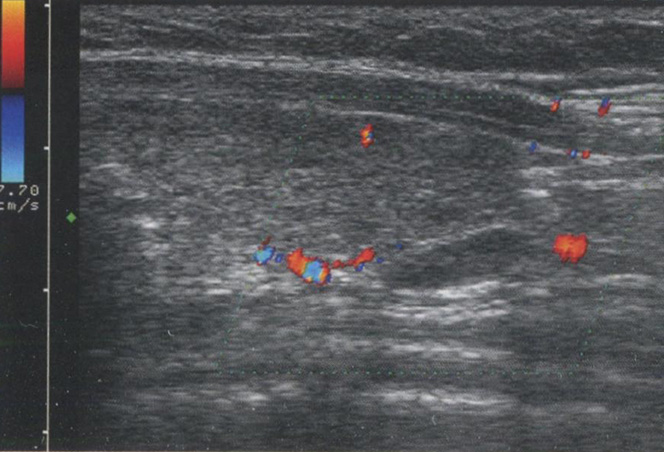

В то же время кистозные структуры проводят звук с очень маленьким затуханием, в результате этого интенсивность звуковых волн за ними намного выше, чем у прилежащих структур. Это приводит к акустическому усилению с ярким сигналом позади кистозных или анэхогенных структур. Это усиление может быть использовано для дифференциации кистозных и солидных узлов в ЩЖ. Рис. 2.12 показывает усиление сигнала.

Рис. 2.12. Усиление сигнала. Кистозные структуры проводят звук с незначительным затуханием, что проявляется в большей интенсивности звуковых волн позади таких образований. Усиление сигнала обычно возникает кзади от кистозного узла